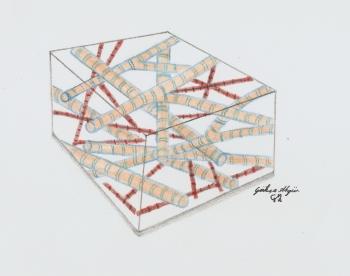

Menisküs 3853 OkunmaPRP (Trombositten Zengin Plazma) Nedir?

Trombositten Zengin Plazma (PRP) Nedir?Kan, sıvı (plazma olarak adlandırılır) içerisinde yüzen küçük katı bileşenler’den (kırmızı hü...

Kıkırdak 15319 OkunmaPRP (Trombositten Zengin Plasma) Nedir?

PRP (Trombositten Zengin Plasma) Nedir?